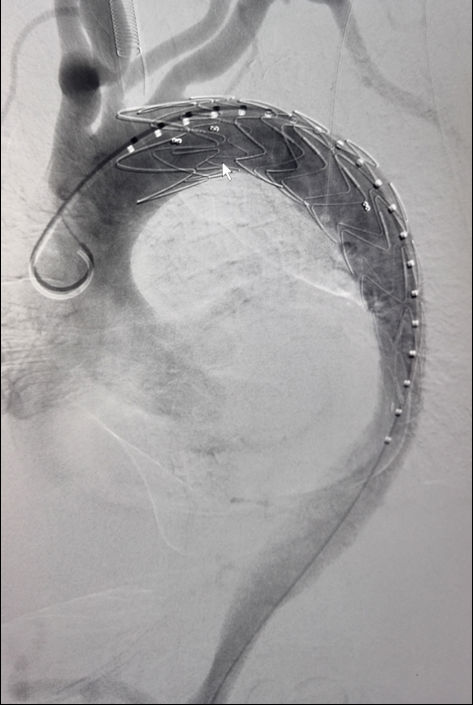

经血管主动脉夹层腔内隔绝术

腔内隔绝治疗主动脉夹层